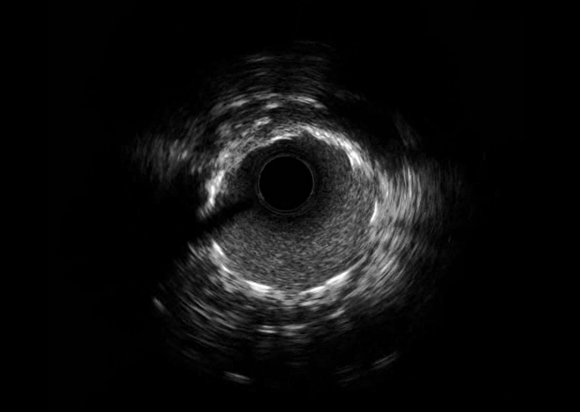

为患者争取放支架的机会----北医三院心血管内科等多科联动在ECMO支持下成功介入治疗一位心肌梗死患者

“谢谢你们,给了我第二次生命!我又回来了。”2021年1月23日,周六上午,心血管内科病房一如既往地忙碌,还没等护士回过神来,回来复诊的老王说,“我专门回来放支架的,有机会做支架我感到高兴啊!” 天底下还有人...